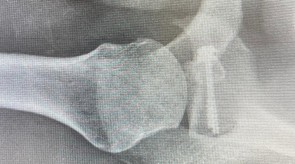

Mediante pequeñas incisiones de 0.5 a 1 cm en puntos estratégicos, se colocan anclajes (tornillos con hilos) o suturas muy fuertes en los tejidos del rodete glenoideo y de la cápsula (reparación de Bankart) para hacerles un “dobladillo” y re-insertarlos en el lugar correcto.

Radiografía de control (procedimiento tipo Latarjet)